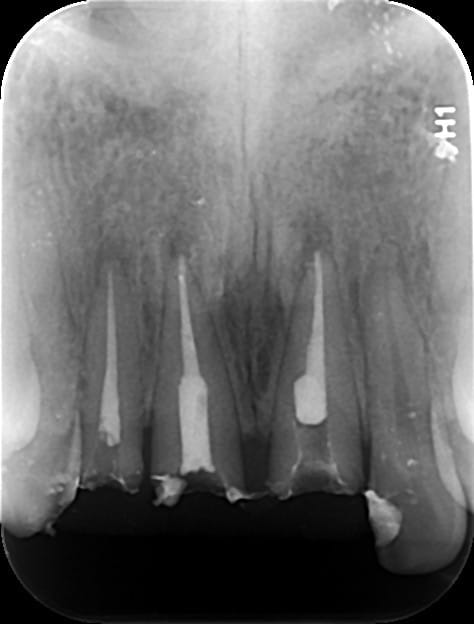

Les densités à la radio et le paralèlisme des tenons laissent penser à un bloc de richmonds solidarisées.

On peut espérer en la faiblesse du ciment.

Il s'agissait de reconstitution foulé Compo + tenon metalliquecollés au Fuji . Tenon que je n'avais jamais vu auparavant ( rainure sur toute la longueure) .

Dépose sans trop de casse et endo correcte dans la foulée .

Et là dessus, zou! 3 coiffes coulées richemond solidarisées!